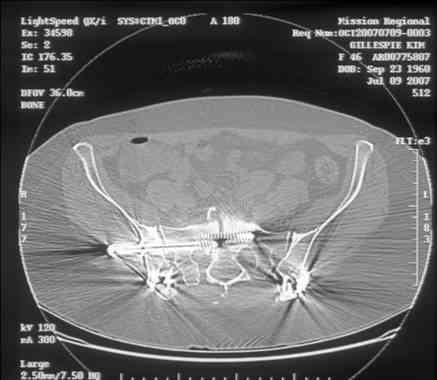

Looking for advice. This is a 48 yo non-smoking female s/p MCC 10 months ago. I do not have the initial injury films. She underwent ORIF as shown on attached file. She is having continued pain in low back/sacral region. Worse with sitting and prolonged walking. Has had pain since surgery. All of her wounds have healed uneventfully. Also has right hip pain laterally. No groin pain. Not aggravated with ROM of the hip. Infection work-up has been negative.

Any thoughts on the broken plate on the pelvic brim and the non-union on the anterior column. Doesn't seem like she's have pain from there.

I can't see the axial CT images well enough to detail the potential sacral issues....can you magnify them?

Here is a magnified view. Sorry about the quality but the CT was scanned into our system.